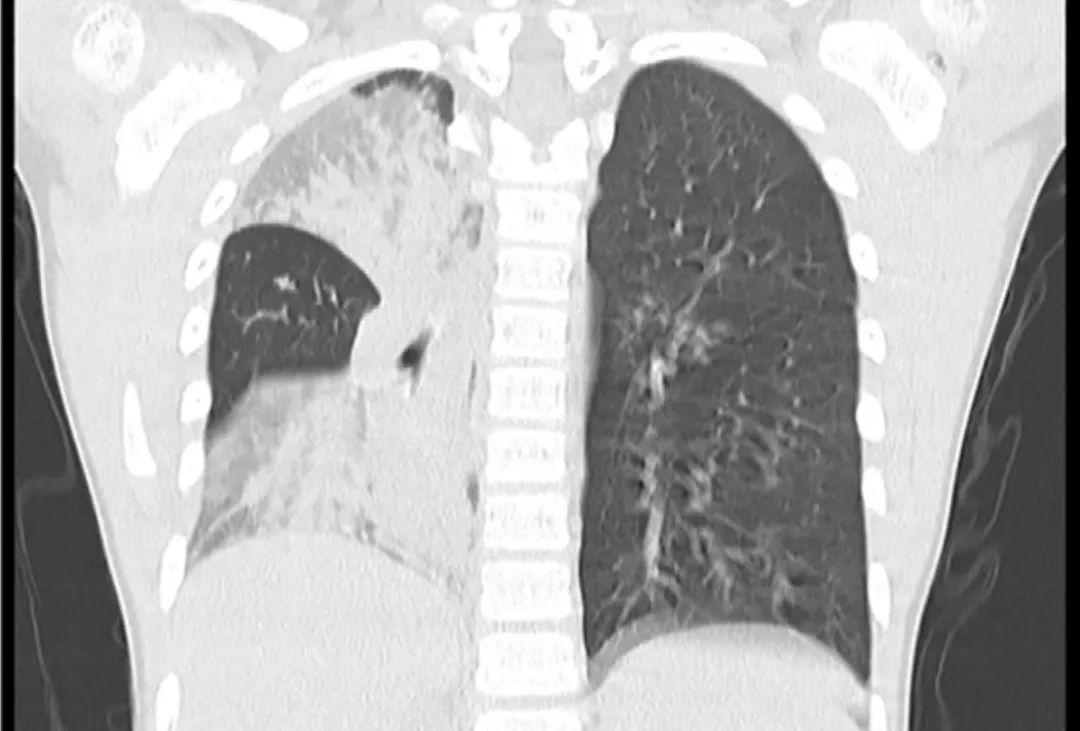

这个CT是肺实变还是肺不张?

肺实变和肺不张是两种常见的肺部疾病,它们在CT影像上表现出不同的特征。肺实变是指肺组织因炎症、渗出等原因导致密度增高,而肺不张则是指肺组织因气道阻塞等原因导致体积缩小。这两种情况在CT影像上的表现有明显区别,对于临床诊断具有重要意义。

在CT影像上,肺实变通常表现为肺实质密度增高,呈均匀或不均匀的实变影。根据一项研究,新型冠状病毒肺炎患者的CT影像中,肺实变表现为斑片状或磨玻璃样密度增高影,常见于肺外周带。这些病灶可能融合成大片实变影,严重时可累及整个肺叶。相比之下,肺不张在CT影像上表现为受累肺叶容积减少,密度增加。肺不张的形态多样,可以是线形、盘状或圆形。例如,线形肺不张表现为肺实质局部呈线状密度增高,几乎总是延伸到胸膜。

这两种影像表现的病理机制也有所不同。肺实变通常是由于肺泡腔内渗出物或细胞成分增多所致。例如,在新型冠状病毒肺炎中,肺泡腔内可见浆液、纤维蛋白性渗出物及透明膜形成。而肺不张则是由于气道阻塞导致肺泡内气体被吸收。气道阻塞的原因可能包括黏液栓、异物、肿瘤等。在CT影像上,肺不张还常伴有叶间裂、支气管、肺血管等结构的异常移位。